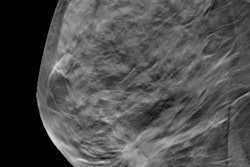

Norwegian researchers have found that screening digital breast tomosynthesis (DBT) requires less compression and pressure than digital mammography. They published their findings online on 25 July in Acta Radiologica.

The study results suggest that DBT could make women's experience of screening mammography more comfortable, as compression can be a negative factor in the screening experience, according to the team led by Gunvor Waade of Oslo Metropolitan University.

Currently, there are no guidelines regarding optimal breast compression for standard digital mammography or for digital breast tomosynthesis, the authors explained. To address this knowledge gap, they conducted a study that compared breast compression parameters and mean glandular dose with digital mammography versus DBT.

The study included 21,729 women who participated in the Digital Breast Tomosynthesis Trial in Bergen (TOBE) as part of BreastScreen Norway between 2016 and 2017. Of these, 11,056 (50.9%) were screened with digital mammography and 10,673 (49.1%) with DBT.

Women who had digital mammography received higher compression forces and pressures than those who underwent DBT, the researchers found. However, those who had DBT exams were exposed to more radiation than those who underwent digital mammography.